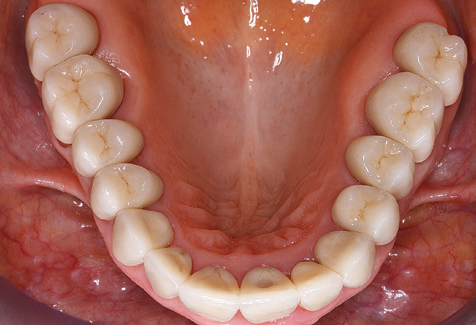

Due to the presence of periodontal disease, SPT was performed every three months in the first years following the insertion. The patient demonstrated a high degree of motivation and good compliance. The pocket depths recorded annually revealed a stable periodontal situation with a BOP index of below five per cent. On the basis of the stable periodontal situation and good cooperation on the patient’s part, the recall interval was extended to every six months as of the sixth year of the prosthetic function phase. Following the change in the recall interval, the respective annual documentation of the periodontal status continued to reveal a stable periodontal situation with no increase in the pocket depths and a BOP index below five per cent (Fig. 2a and b).

The ten-year check-up revealed no indications of advancing clinical attachment loss or peri-implant bone substance loss (Fig. 3).

Fig. 2: The pocket depths recorded annually with six-monthly SPT display no increasing trend and a BOP index of below 5 per cent with a largely inflammation-free periodontal situation. a) PERIO status in 2011 (after five years with implants). b) PERIO status in 2016 (after ten years with implants).